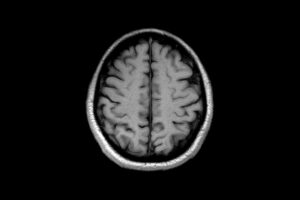

Facts About Your Brain You Should Know